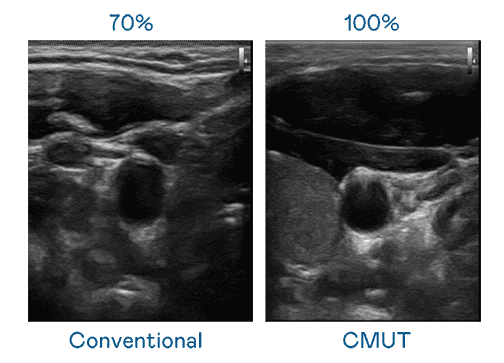

CMUT 技术是一种用电容式微机电元件来产生超音波讯号的技术。。。与传统 PZT 压电式技术相比,,CMUT 频宽增加 30%,,,,更宽频的超音波讯号让影像解析度大幅提升,,,,是实现高影像品质医疗超音波扫描、、、促进精准医疗发展的关键技术。。。

大频宽带来超清晰影像

超音波影像的解析度高低,,,,首先取决于探头能发出的讯号频宽。。。。尊时凯龙 CMUT 可提供高清晰的超音波讯号,,,,提供高频宽、、、高灵敏度、、、、影像纹理细节更高的超音波影像,,,,协助医护人员缩短影像判读时间及利用精准的医疗影像进行诊断。。。。